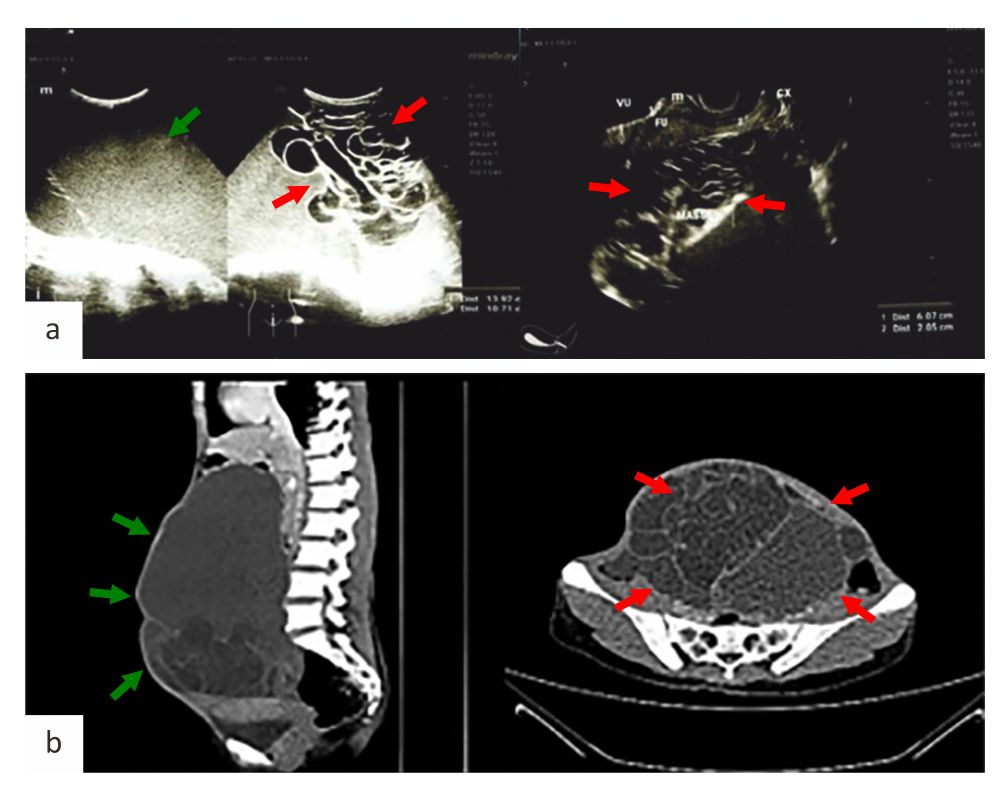

Imaging studies, including ultrasound (US) and contrast-enhanced computed tomography (CT) scans, were done (Figure 2). Her US examination revealed a large mass in the right ovary, which was suspected of a mucinous-type malignancy. The CT scan of the whole abdomen revealed a large, septated cystic mass in the right ovary, measuring 12.8 × 22.1 × 25.8 cm, without signs of infiltration into surrounding organs. Malignancy was suspected, and the tumor marker cancer antigen 125 was elevated at 194 U/ml.

Figure 2. US and CT scan imaging. (a) US image shows a large mass in the right ovary, suspected malignancy of a mucinous type (green arrow) with >10 locules (red arrows); (b) CT of the whole abdomen image shows a large (green arrows), septated cystic mass (red arrows) in the right ovary, measuring 12.8 × 22.1 × 25.8 cm, without signs of infiltration into surrounding organs. CT=computed tomography; US=ultrasound